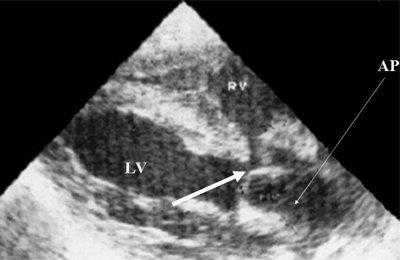

Характерными особенностями выраженной объемной перегрузки правого желудочка являются дилатация желудочка, при которой толщина миокарда не превышает верхней границы нормы, увеличение правого предсердия, парадоксальный характер движения межжелудочковой перегородки и увеличение амплитуды движения трикуспидального клапана (рис. 2, 3).

Рис. 2. Длинная ось сердца. Объемная перегрузка правого желудочка при дефекте межпредсердной перегородки. Объем сброса крови превышает 200% МОС. Отмечается выраженная дилатация правого желудочка.

Для левого желудочка признаком объемной перегрузки являются увеличение полости левого предсердия и желудочка, а также экскурсии межжелудочковой перегородки и миокарда задней стенки левого желудочка (рис. 4).

Рис. 4. Объемная перегрузка левых отделов сердца. В- и М-сканирование. Отмечается усиление экскурсии межжелудочковой перегородки и миокарда задней стенки левого желудочка.

IVS - межжелудочковая перегородка, MLV - миокард левого желудочка, LV и RV - левый и правый желудочек.